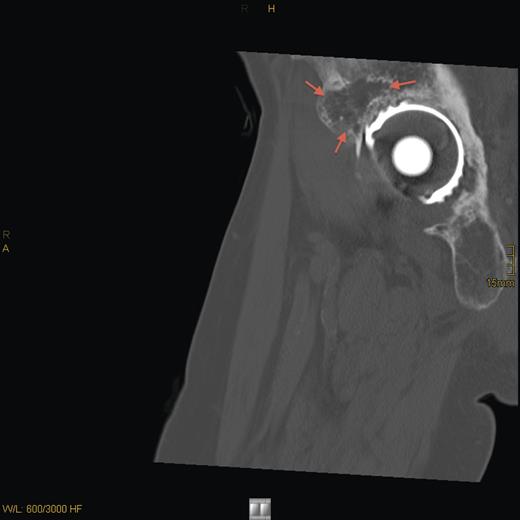

Eight years later, the patient presented with hip pain on the same side over a longer period. CT scan and MRI revealed tumor recurrence (Fig. 2) on the dorsomedial circumference of the acetabulum with a bone defect 2 cm in diameter. Signs of loosening of the cup of the hip arthroplasty were considered secondary. Biochemical evaluation revealed hypophosphatemia with 0.69 mmol/l of phosphate, normal serum calcium of 2.42 mmol/l and a secondary hyperparathyroidism with parathyroid hormone of 85.7 ng/l (normal range: 15–65 ng/l). An octreotide scan of the right hip showed massive enhancement of the acetabulum. Assessment of FGF-23 was inconclusive.

CT sagittal scan showing a suspected osteolytic lesion (arrows) in the right os ilium (8 years after primary resection).